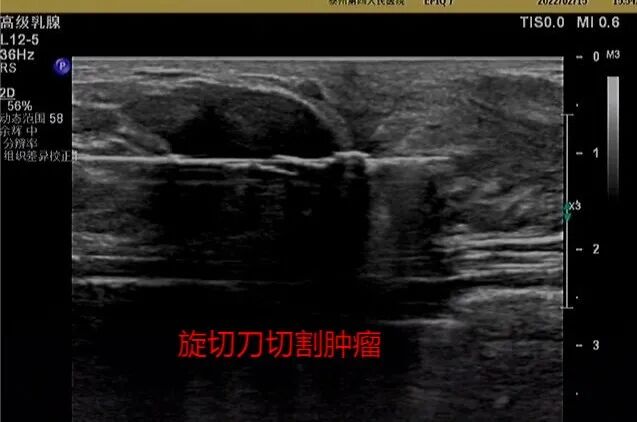

麦默通旋切术是在超声定位引导下,通过计算机控制的真空辅助高速旋切乳房治疗性诊断性微创手术,它可以准确的一次切除多个乳房肿块及对肿块进行病理活检,及时发现乳腺癌。

2月18日,泰州四院超声科专家汤四新、李娅成功为王女士进行手术,解决了她的“心头之忧”,既切除了乳腺结节,又保住了乳房的美观。手术采用局部麻醉,在B超系统的引导下,由旋切探针从乳房肿块上3-4mm处插入待检区域,进行轻柔的真空抽吸和切割,完成肿块的切除,为检查和评估取出组织。手术仅有2mm长切口,不用缝针,单用普通胶贴贴合即可。